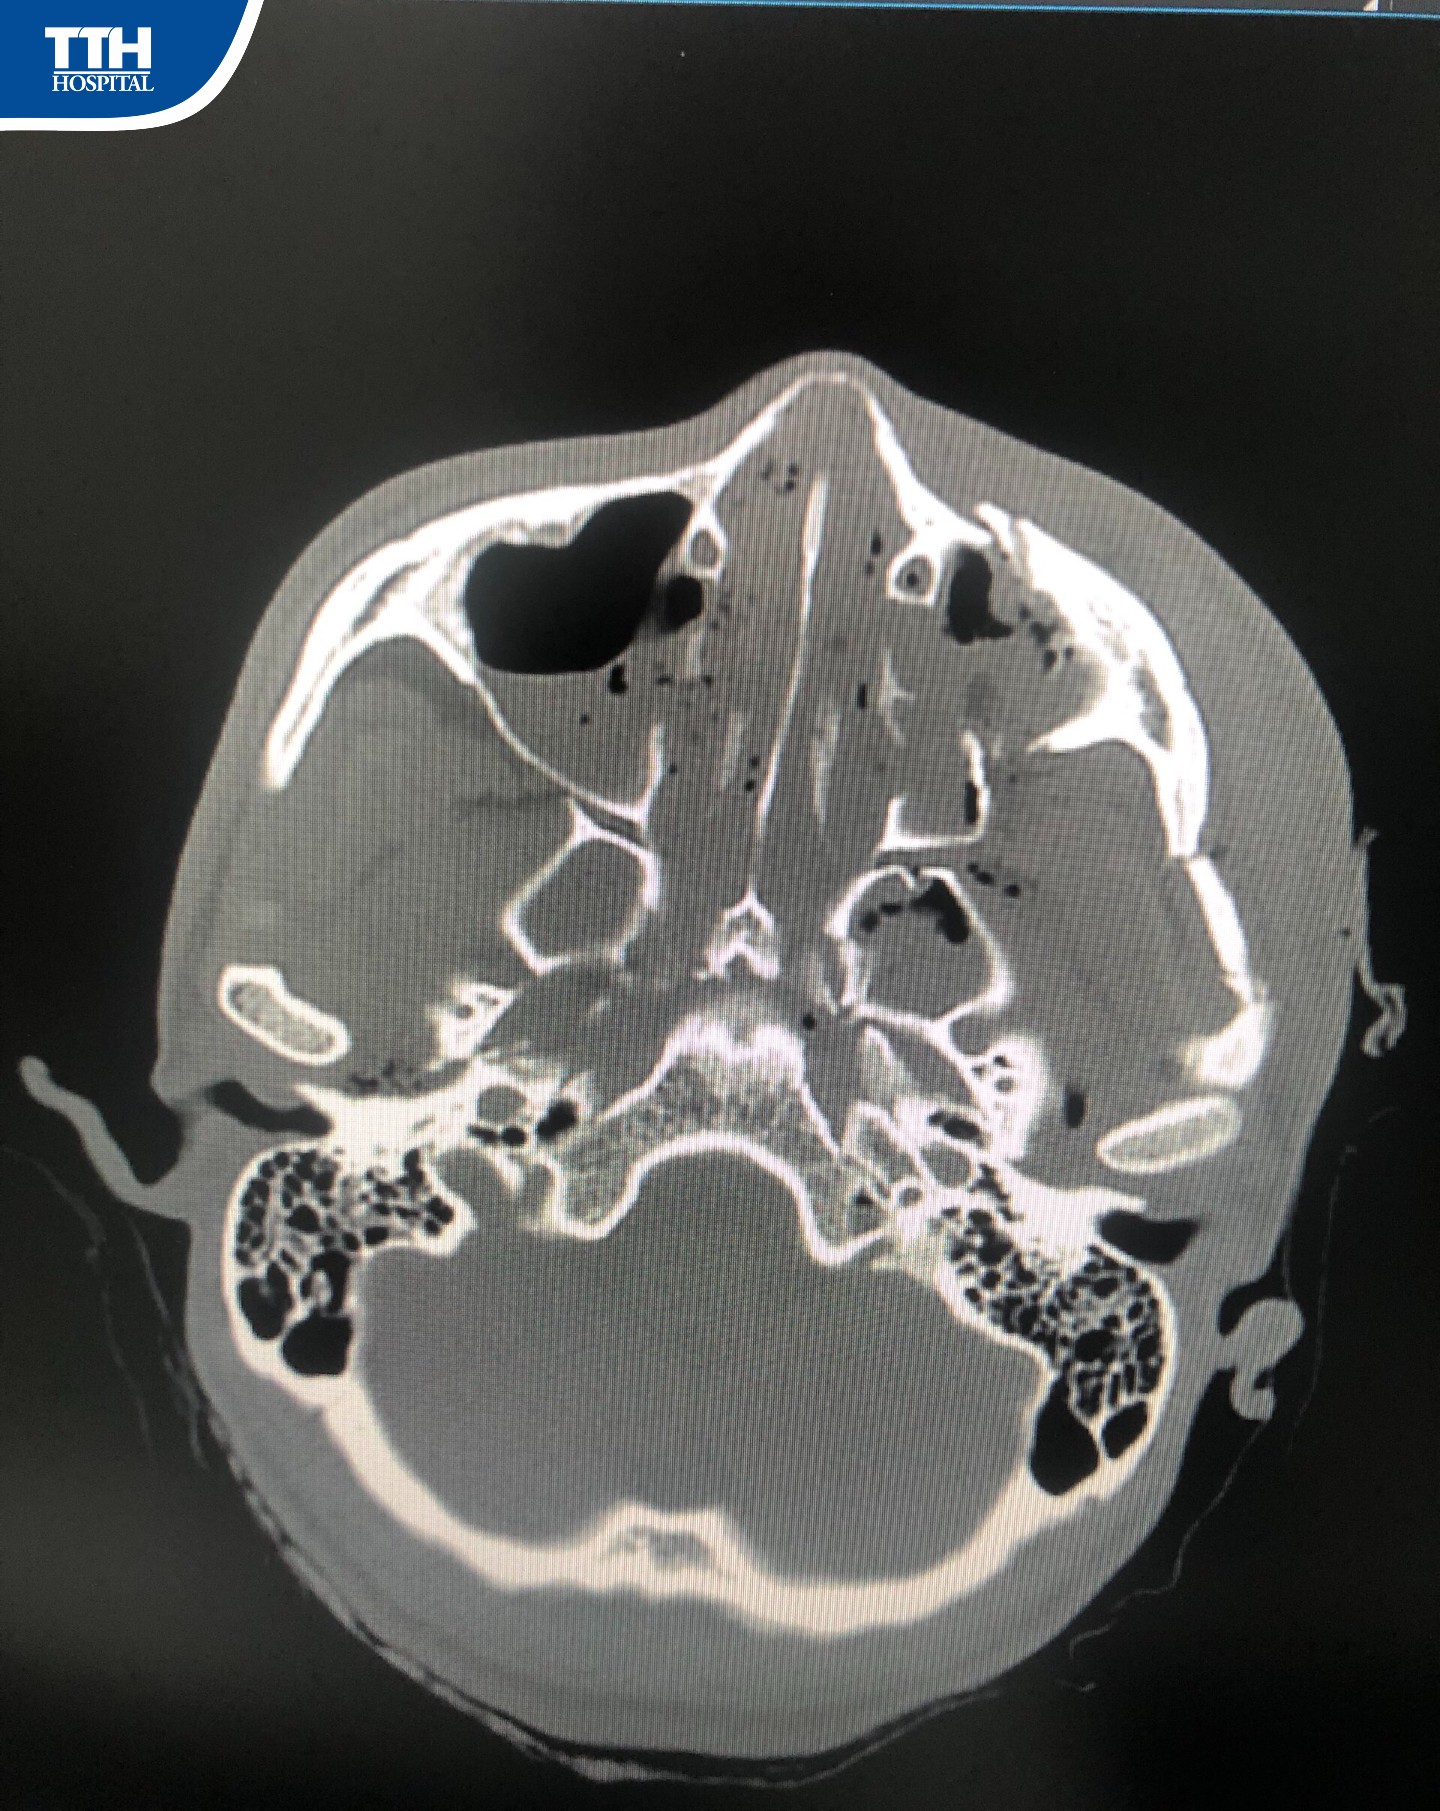

Vừa qua, Bệnh viện Đa khoa TTH Hà Tĩnh tiếp nhận bệnh nhân T.X.C (1996, Quỳnh Thanh, Quỳnh Lưu, Nghệ An), bệnh nhân cho biết lý do nhập viện khoa Răng Hàm Mặt là vì: ‘‘Cách đây 7 tháng đã đến Bệnh viện Đa khoa TTH Hà Tĩnh phẫu thuật kết hợp xương hàm trên, sau quá trình mổ ăn nhai tốt, mặc dù trên địa bàn Nghệ An có rất nhiều Bệnh viện mổ được nhưng Bệnh nhân và gia đình vẫn tin tưởng quay lại Bệnh viện Đa khoa TTH Hà Tĩnh để xin tháo nẹp’’.

Theo BSCKI Trần Đức Hải – Trưởng khoa Răng Hàm Mặt Bệnh viện Đa khoa TTH Hà Tĩnh cho biết: ‘‘Ca phẫu thuật diễn ra thuận lợi trong khoảng gần 1 giờ. Sau phẫu thuật tháo phương tiện kết hợp xương hàm mặt, người bệnh hồi phục nhanh, từ ngày thứ 2 sau mổ. Sau 3-5 ngày, người bệnh có thể đi lại, sinh hoạt và xuất viện’’.